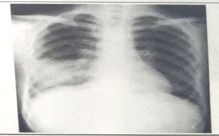

試題1:男性,26歲,受涼后寒顫高熱,咳嗽,咳鐵銹色痰5天(2分)

答案:D